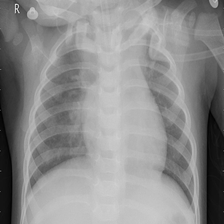

图像分类是计算机视觉的重要领域,它的目标是将图像分类到预定义的标签。许多研究者提出了很多不同种类的神经网络,并极大地提升了分类算法的性能。本次实践将训练ResNet模型实现对胸部CT影像的分类,以区分新冠肺炎患者、病毒性肺炎患者以及正常人。

新冠肺炎在全球爆发以后,来自卡塔尔、孟加拉国、巴基斯坦以及马来西亚的研究人员与医生合作,建立了一个包含正常人、病毒性肺炎患者、新冠肺炎患者的胸部CT影像的数据集。数据集包含1200个新冠阳性患者的影像、1341个正常人的影像和1345个病毒性肺炎患者的影像。

图1的真实标签:正常肺部,预测结果:正常肺部

图2的真实标签:病毒性肺炎,预测结果:病毒性肺炎

图3的真实标签:新冠肺炎,预测结果:新冠肺炎